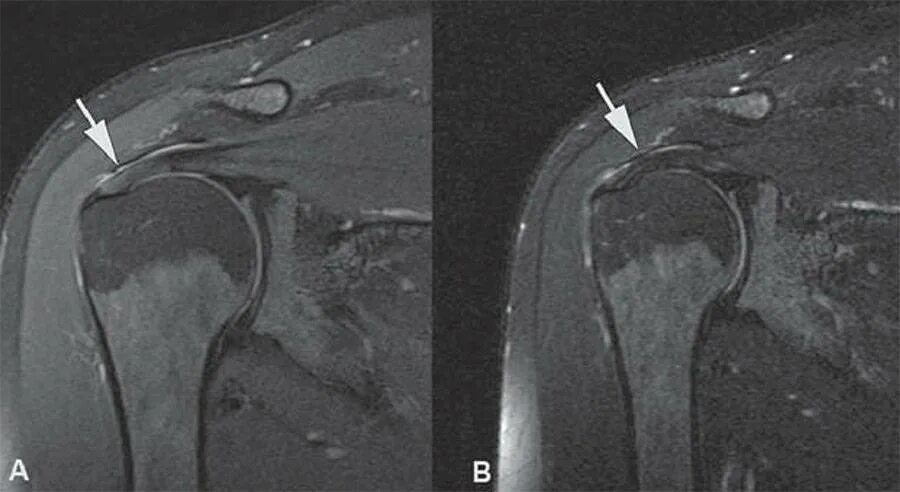

Мрт суставов пермь